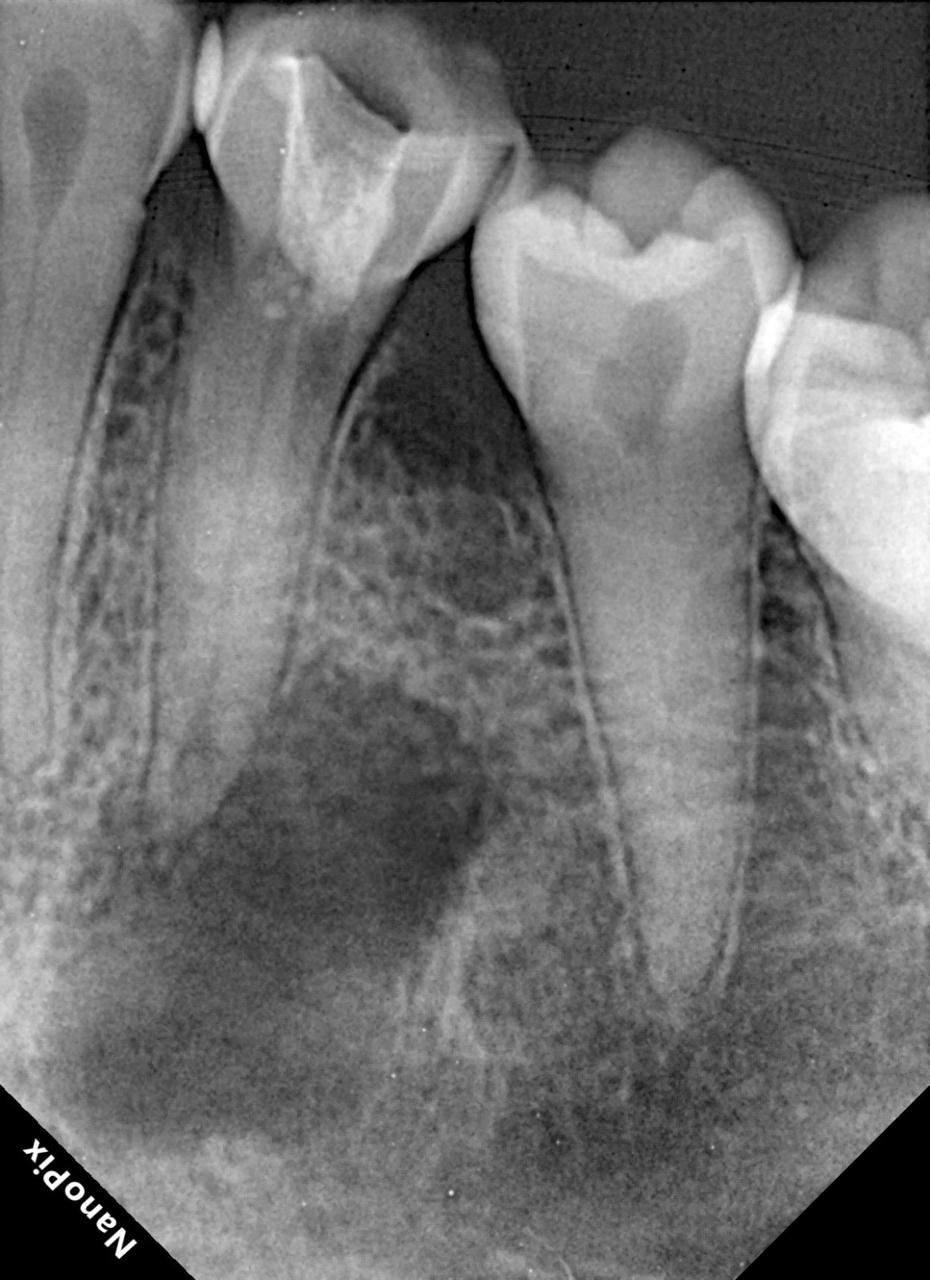

There are 2 types of x rays, intraoral and extra oral. Intraoral X rays are taken inside the mouth and an extra oral x-ray is taken outside the mouth. Intraoral X rays are more common and help your dentist in:

- Looking at the roots of teeth for root canal

- Checking bone and jaw health

- Identifying the extent of gum disease